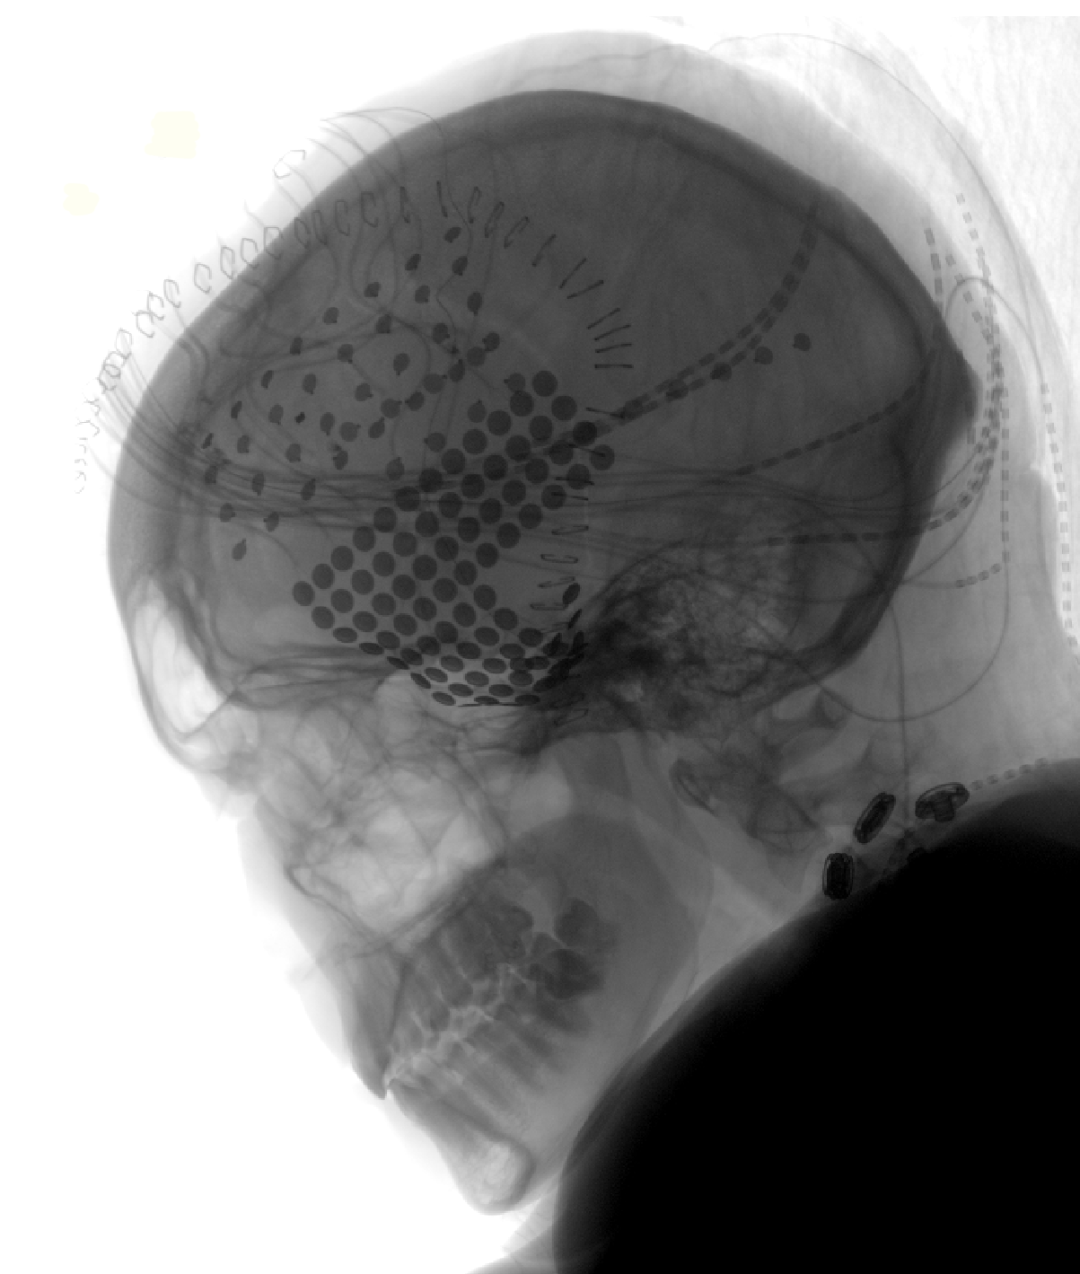

图B为X光片下,一名患者的电极覆盖图。每一个点代表着一个电极。